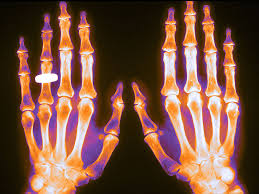

Esta es la segunda entrega de la Folia DOC  dedicada a osteoporosis. La primera se enfocó en el diagnóstico, prevención y medidas no farmacológicas, y en esta se aborda el tratamiento farmacológico. El mismo variará según el riesgo estimado de fractura, la consideración de la eficacia y seguridad de los diferentes fármacos, la conveniencia de su administración y las preferencias de las pacientes. FoliaDOC, Fundación FEMEBA, 27 de enero de 2025.